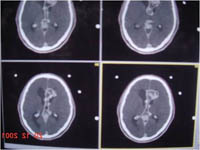

Radiosurgery Gallery